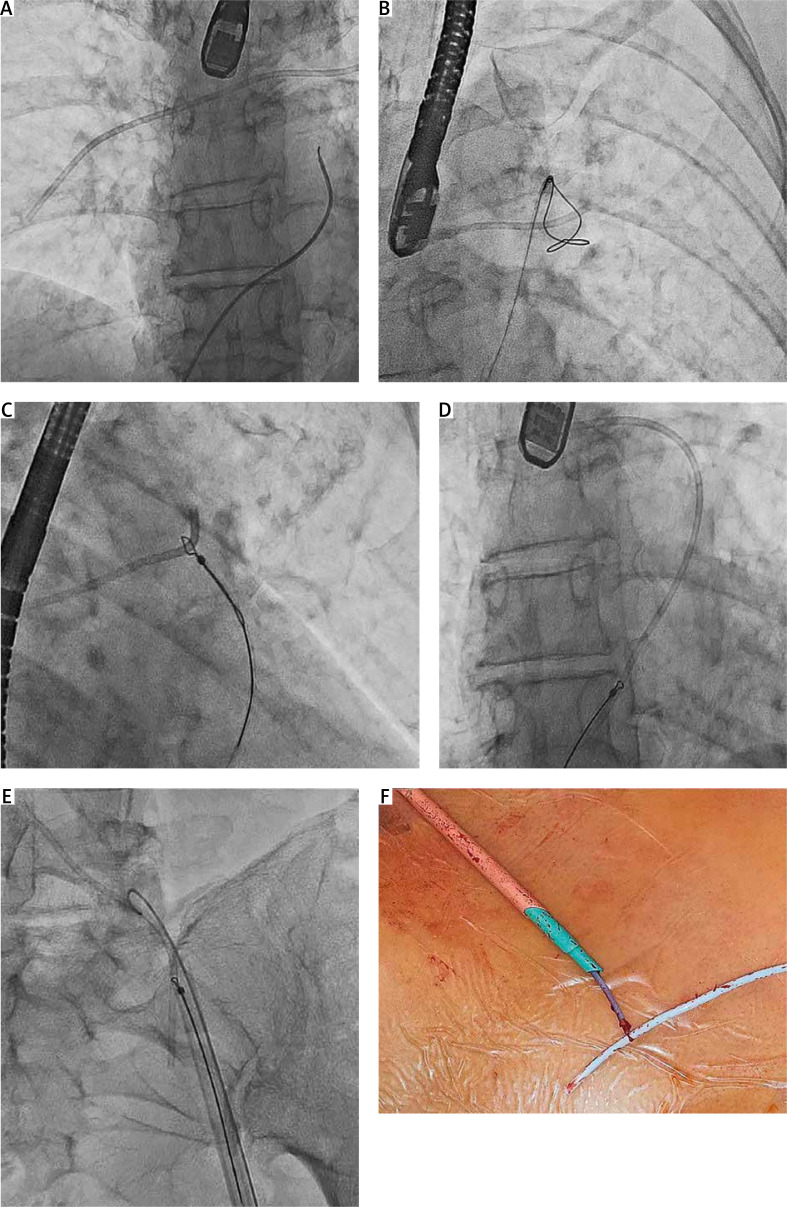

The use of venous access ports carries a risk of complications, including catheter fracture with migration of catheter fragments into the pulmonary arteries. Experience in removing broken catheters is limited and there are no special tools. We present 4 cases of catheter removal using the available lassos/lasso catheter and tools designed for transvenous lead extraction and coronary sinus lead implantation via a femoral and subclavian approach. All four procedures were successful and without complications.